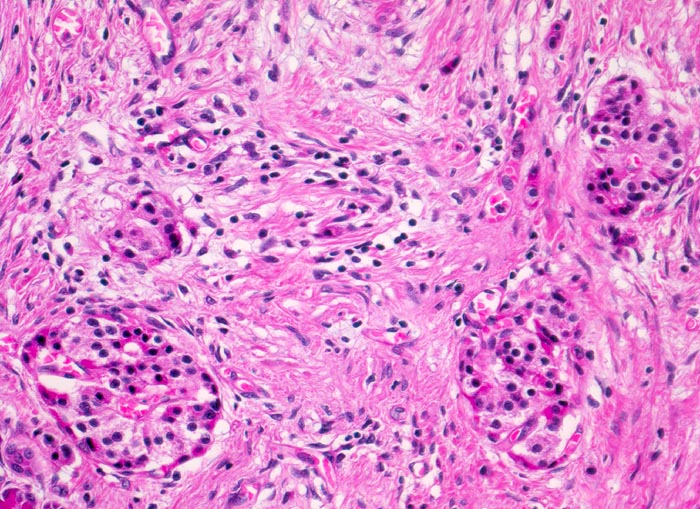

Während die Azini das exokrine Pankreasparenchym zunehmend fibrosieren und schliesslich ganz verschwinden, bleibt das endokrine Pankreas relativ gut erhalten. Nach Verschwinden der Azini sind im fibrosierten Gewebe Pankreasinseln zurückgeblieben. Geringgradiges lymphoplasmazelluläres Entzündungsinfiltrat.

Durch das Verschwinden des exokrinen Pankreas rücken die Inseln näher zueinander und erscheinen zahlreicher als normal. Dies führt zum fälschlichen Eindruck einer Hyperplasie der Pankreasinseln.